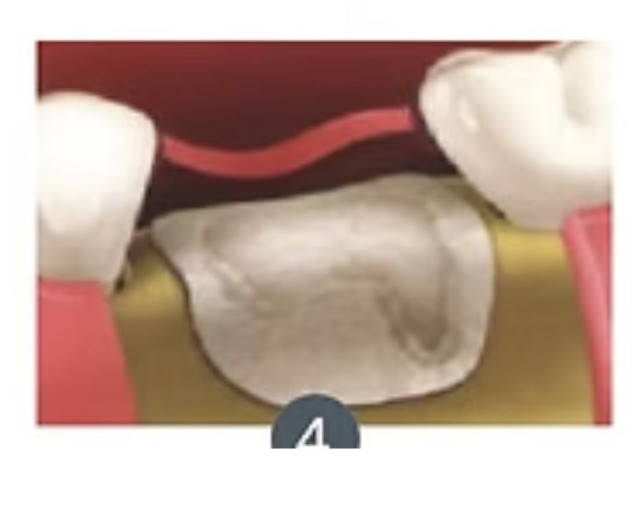

Exodoncia+ Preservación de alvéolo

La exodoncia con preservación del alveolo es un procedimiento dental que combina la extracción de un diente con la protección y preservación del alvéolo dental (la cavidad en el hueso donde estaba el diente) para facilitar futuras restauraciones dentales, como la colocación de implantes dentales.